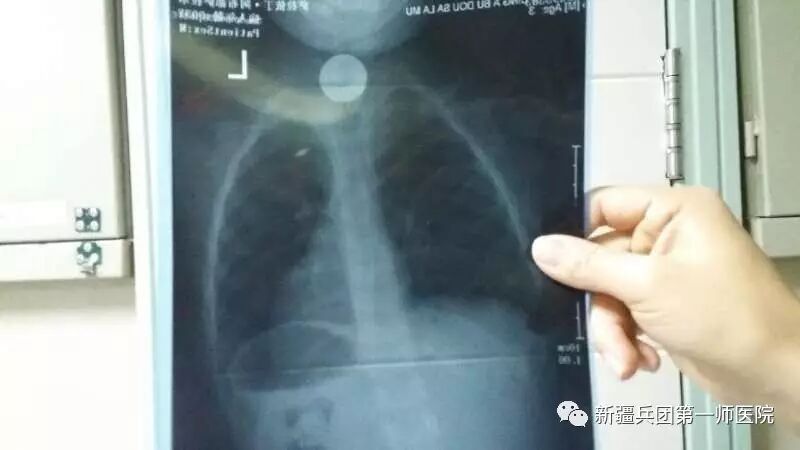

- 12-131【医共体动态】二团分院开展危重孕产妇

- 12-122第一师医院召开“6S”管理第三批推广